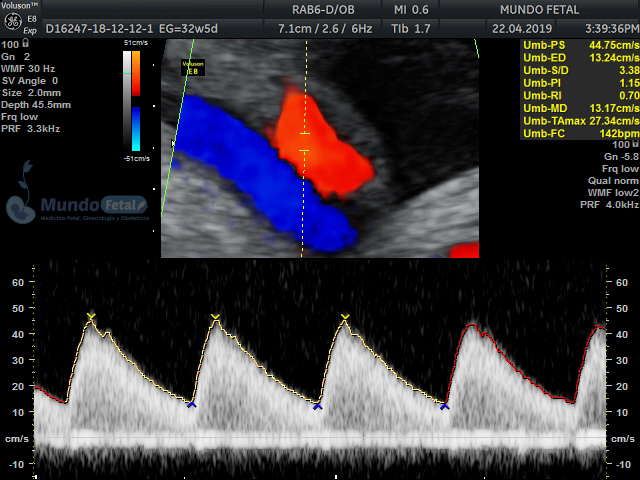

Mediante esta técnica ultrasonográfica, evaluamos en tiempo real al bebe y monitoreamos electrónicamente la frecuencia cardiaca fetal, vigilando los siguientes parámetros:

A cada parámetro se le asigna un puntaje basado en una escala del 0 al 10. Se ha propuesto que en estados fetales alterados por disminución del oxígeno se alteran los parámetros de manera que podemos predecir el estado fetal evaluando estos puntos.